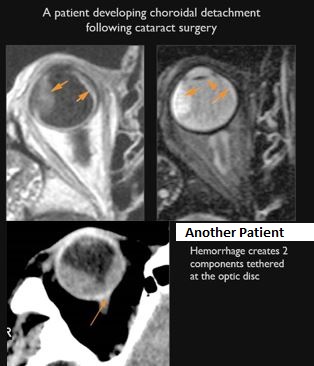

There is evidence of a subretinal, subchoroidal, subhyaloid or intravitreous hemorrhage or other fluid collection. [Yes/No]

The junctions of the optic sheath/nerve and eye are abnormal. [Yes/No]

There is evidence of hemorrhage in or along the optic nerve and/or sheath. [Yes/No]